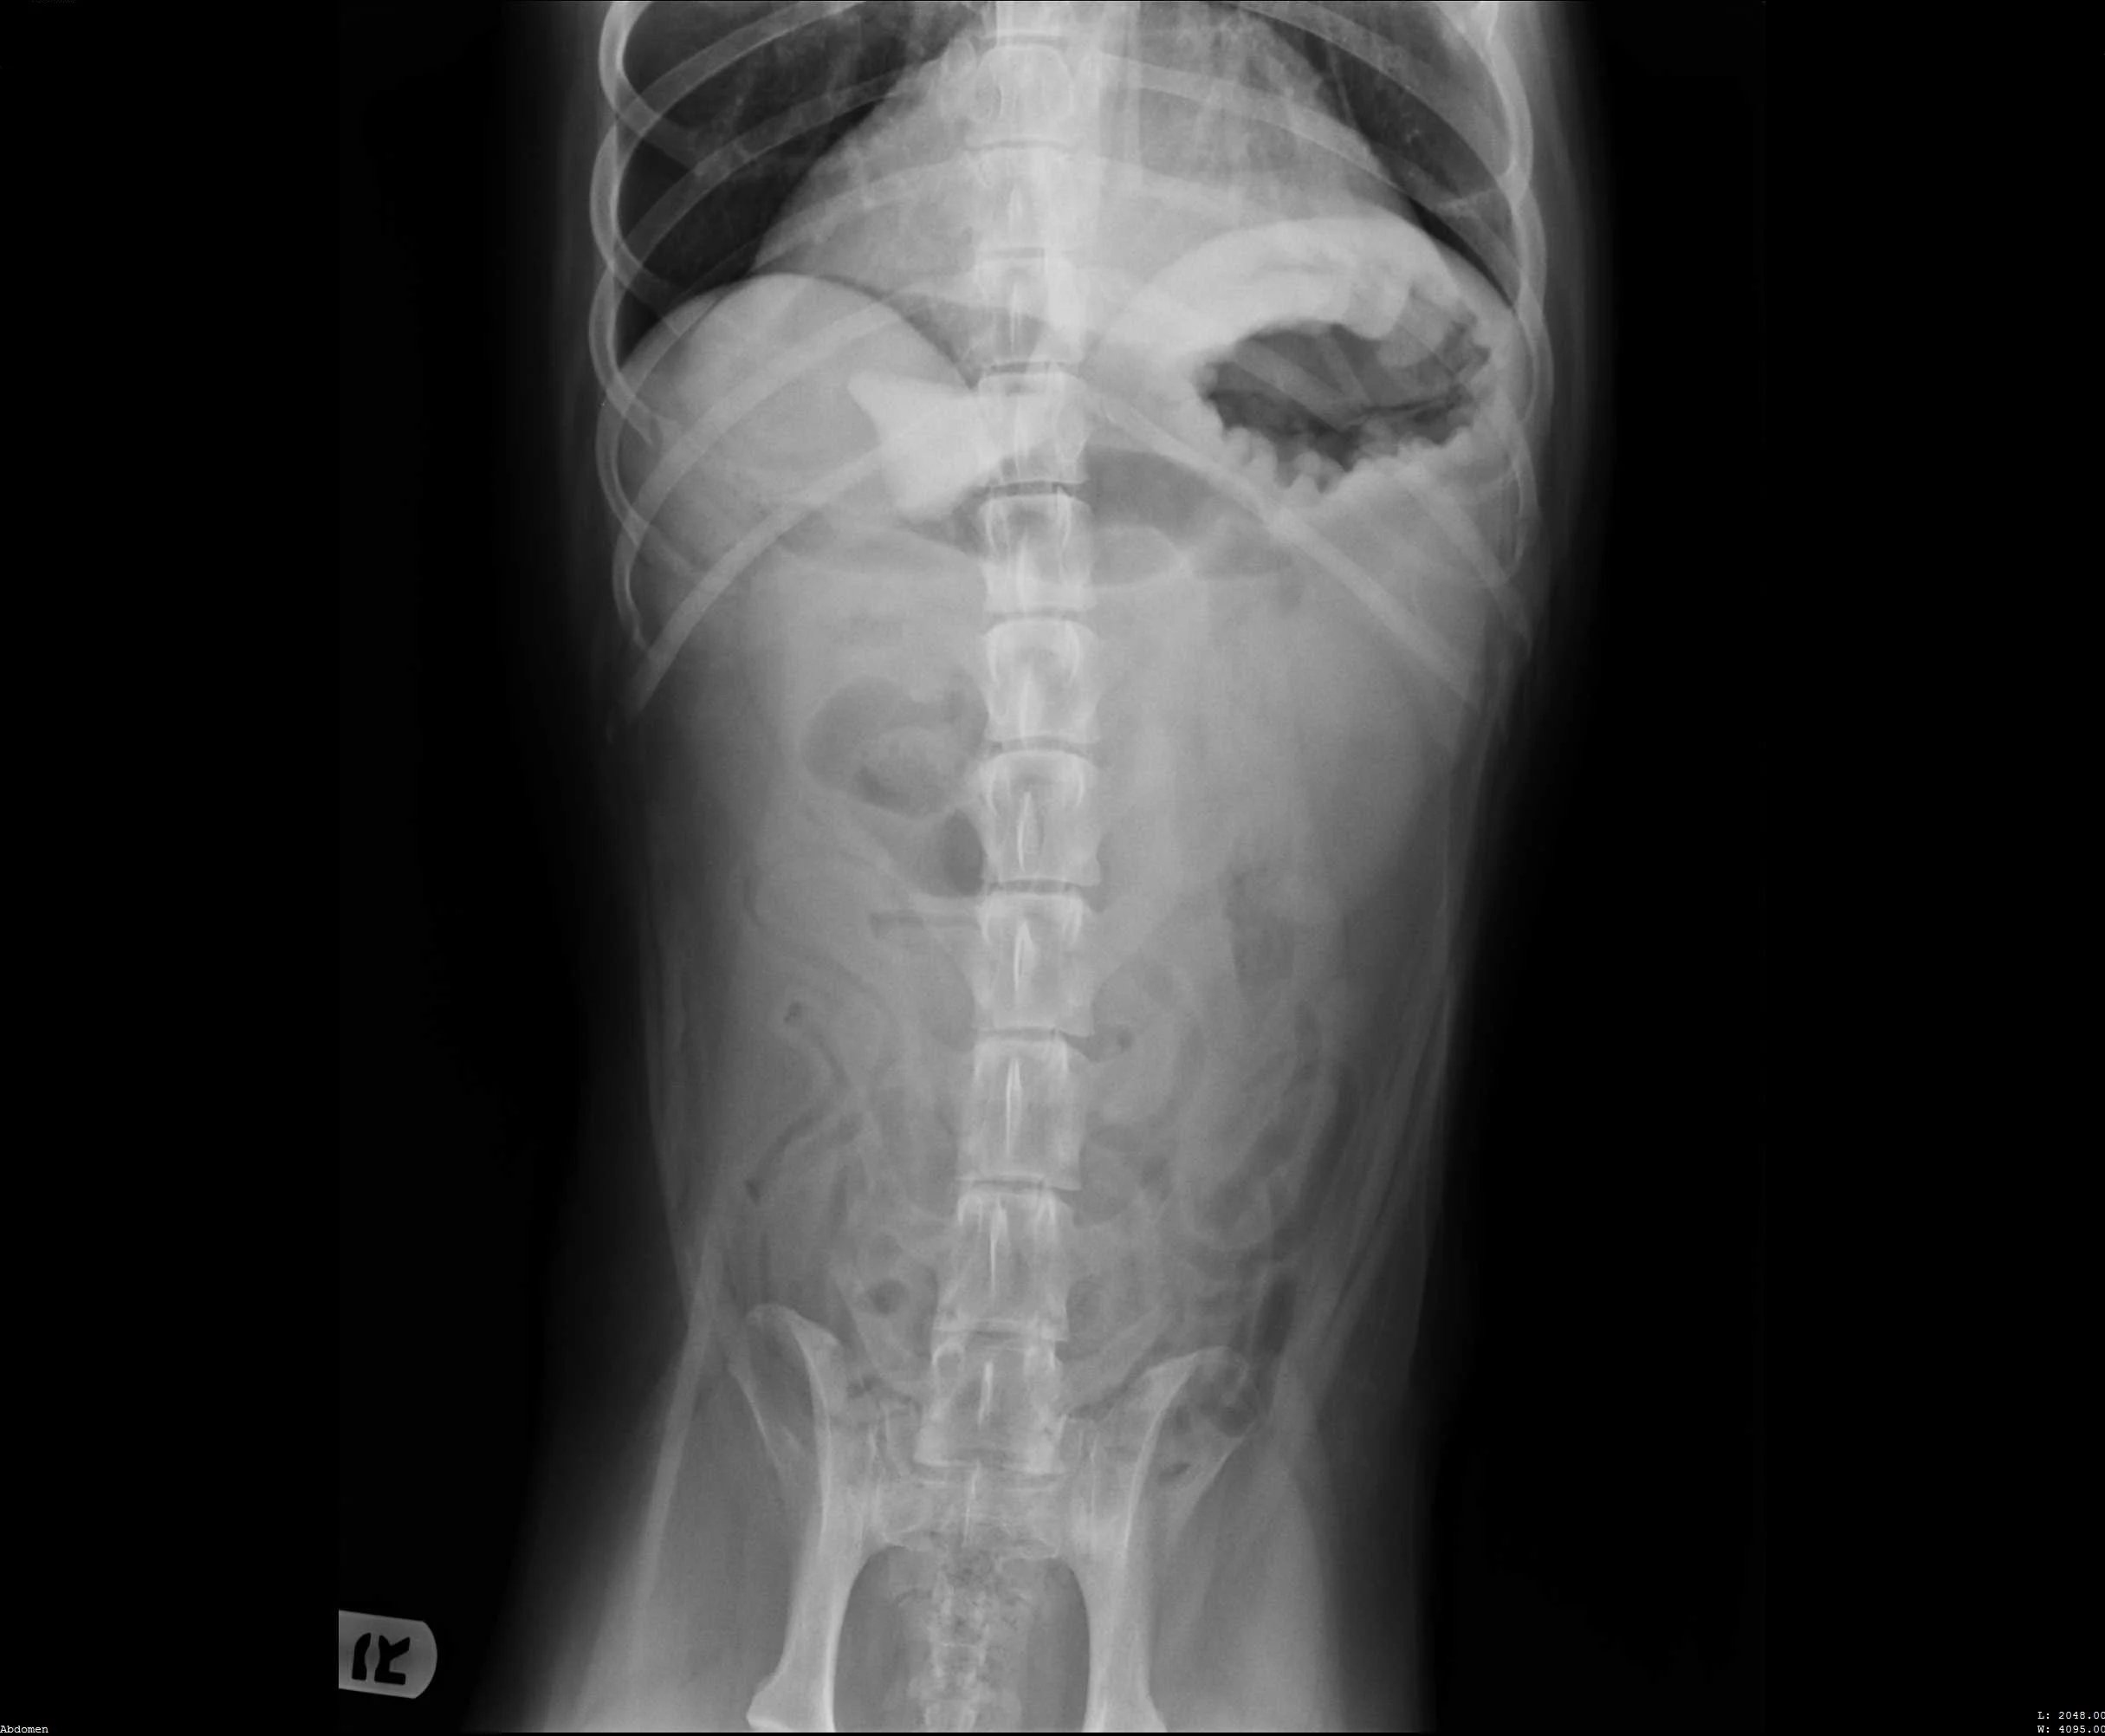

Abdominal radiographs revealed a rock in the patient’s stomach, leading to a diagnosis of a gastric foreign body with outflow obstruction and a secondary finding of megaesophagus.

Ventrodorsal abdomen